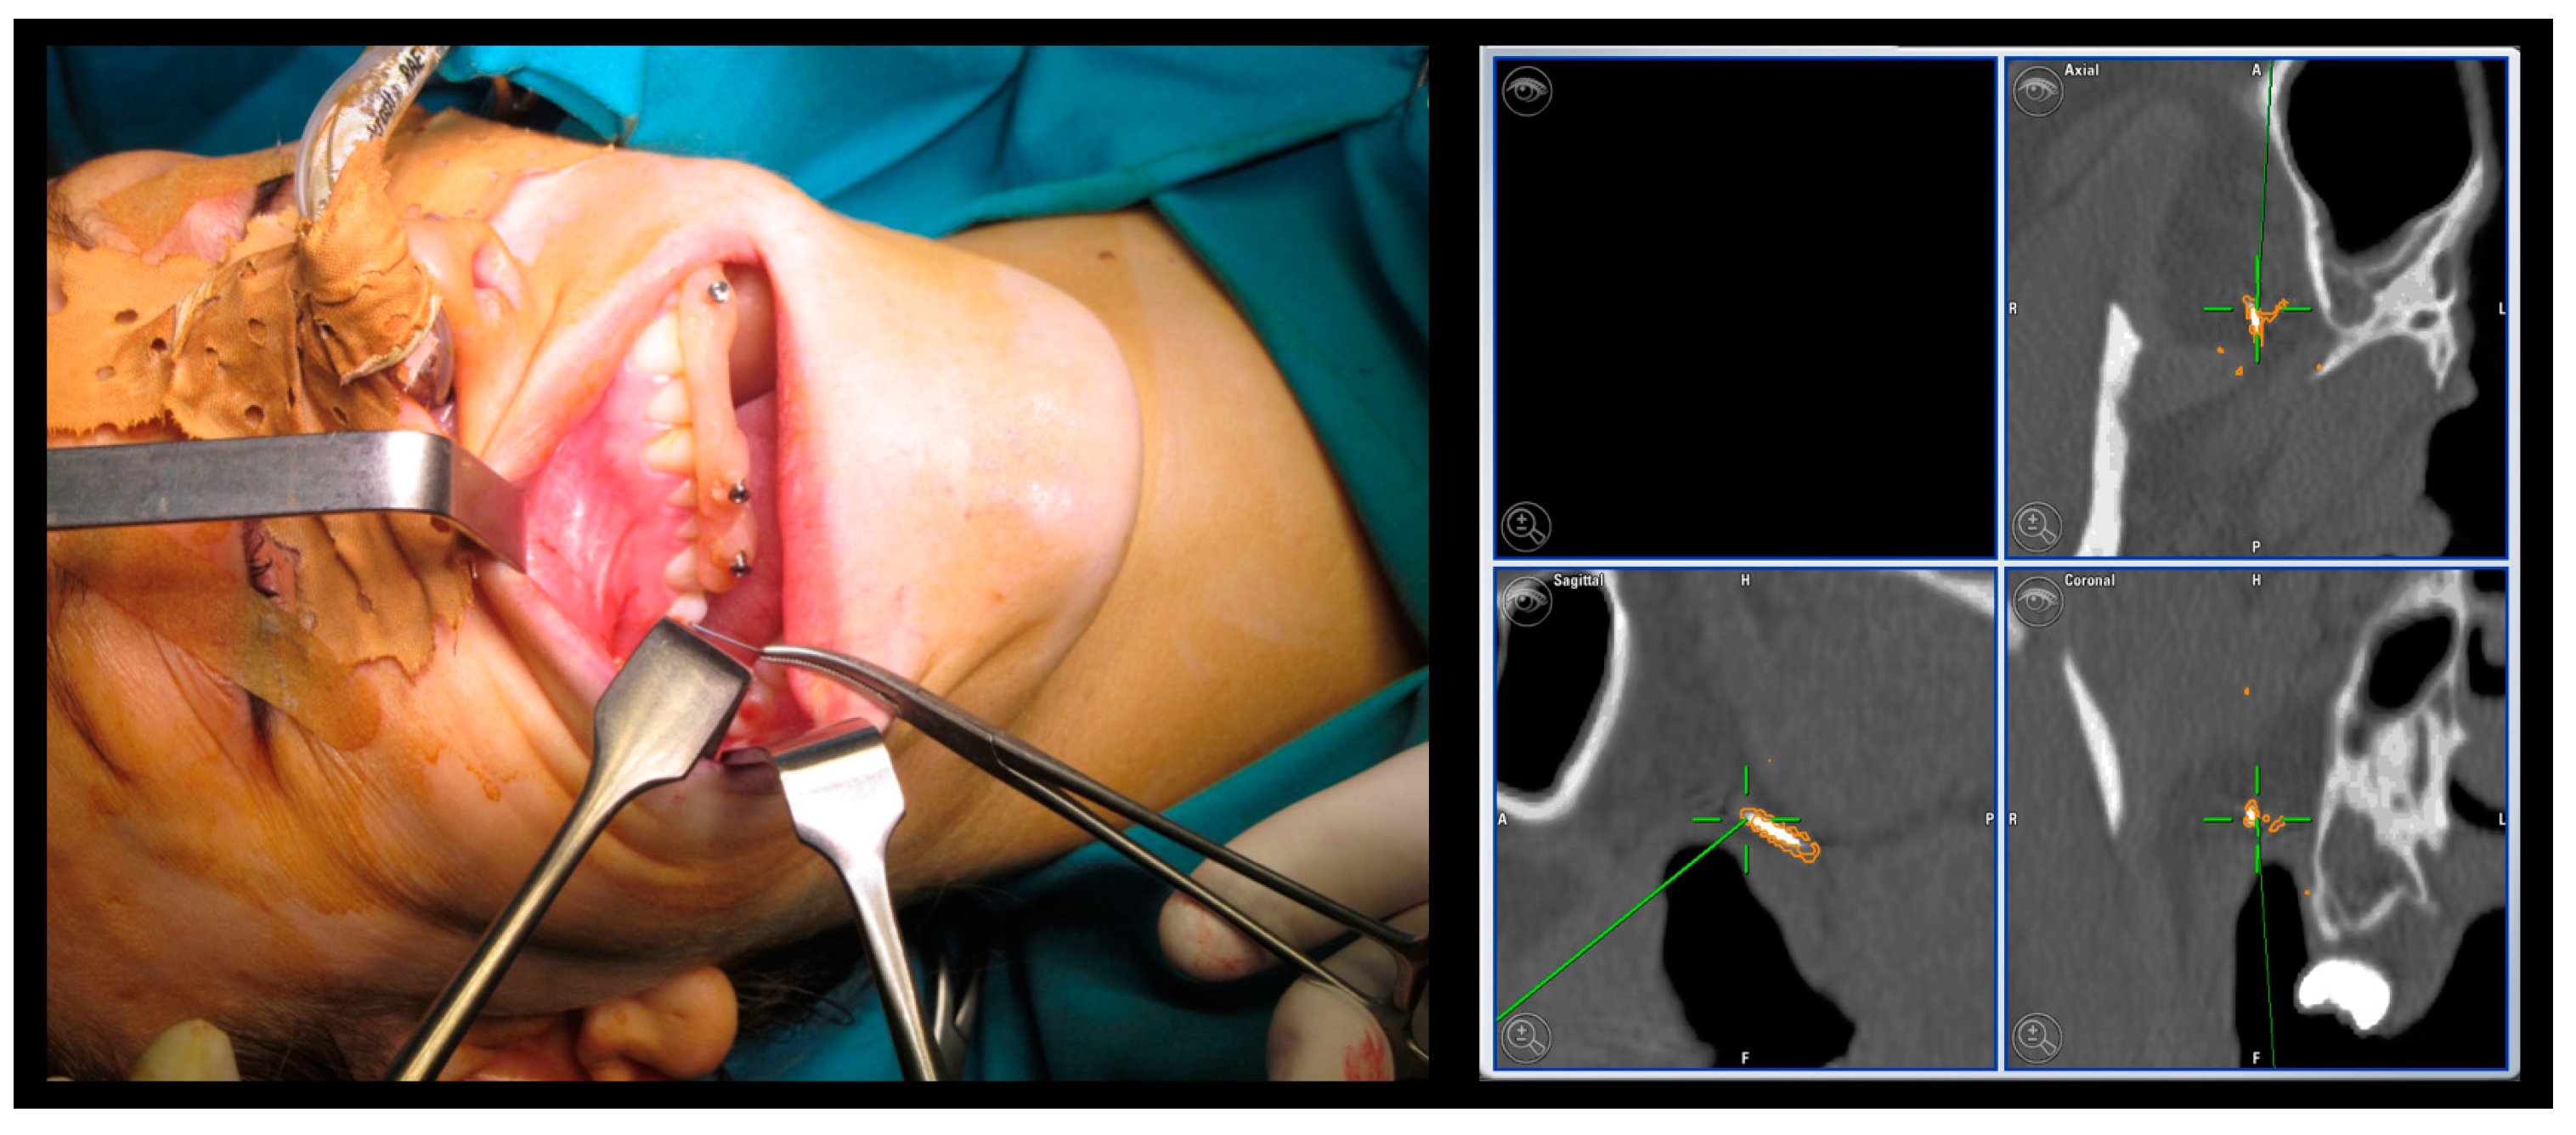

- Invasive fiducial markers: they are normally made up of self-tapping titanium screws inserted into bone through a cutaneous or mucosal access. They are extremely precise, small in size, and do not undergo modifications from the image acquisition phase to the operative time. Due to their characteristics, they can be applied in large numbers. The disadvantages are linked to the invasiveness of their positioning.

| Case 1 Foreign body | 1.00 mm | |||